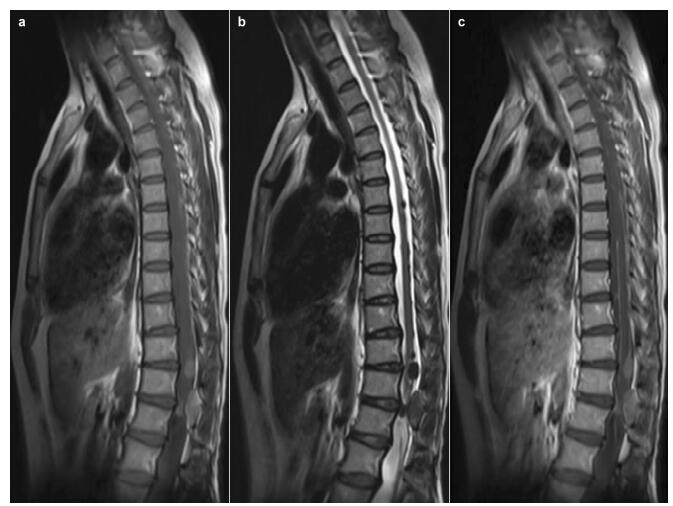

20170308102006 Figure 2 Sagittal magnetic resonance (MR) images. Multi-nodules of T6 through L1, hyperintense on the T1 weighted image (a), hypointense on the T2 weighted image (b), and homogenous enhancement of the lesions and linear enhancement of the spinal pia mater on T1-weighted images (c).